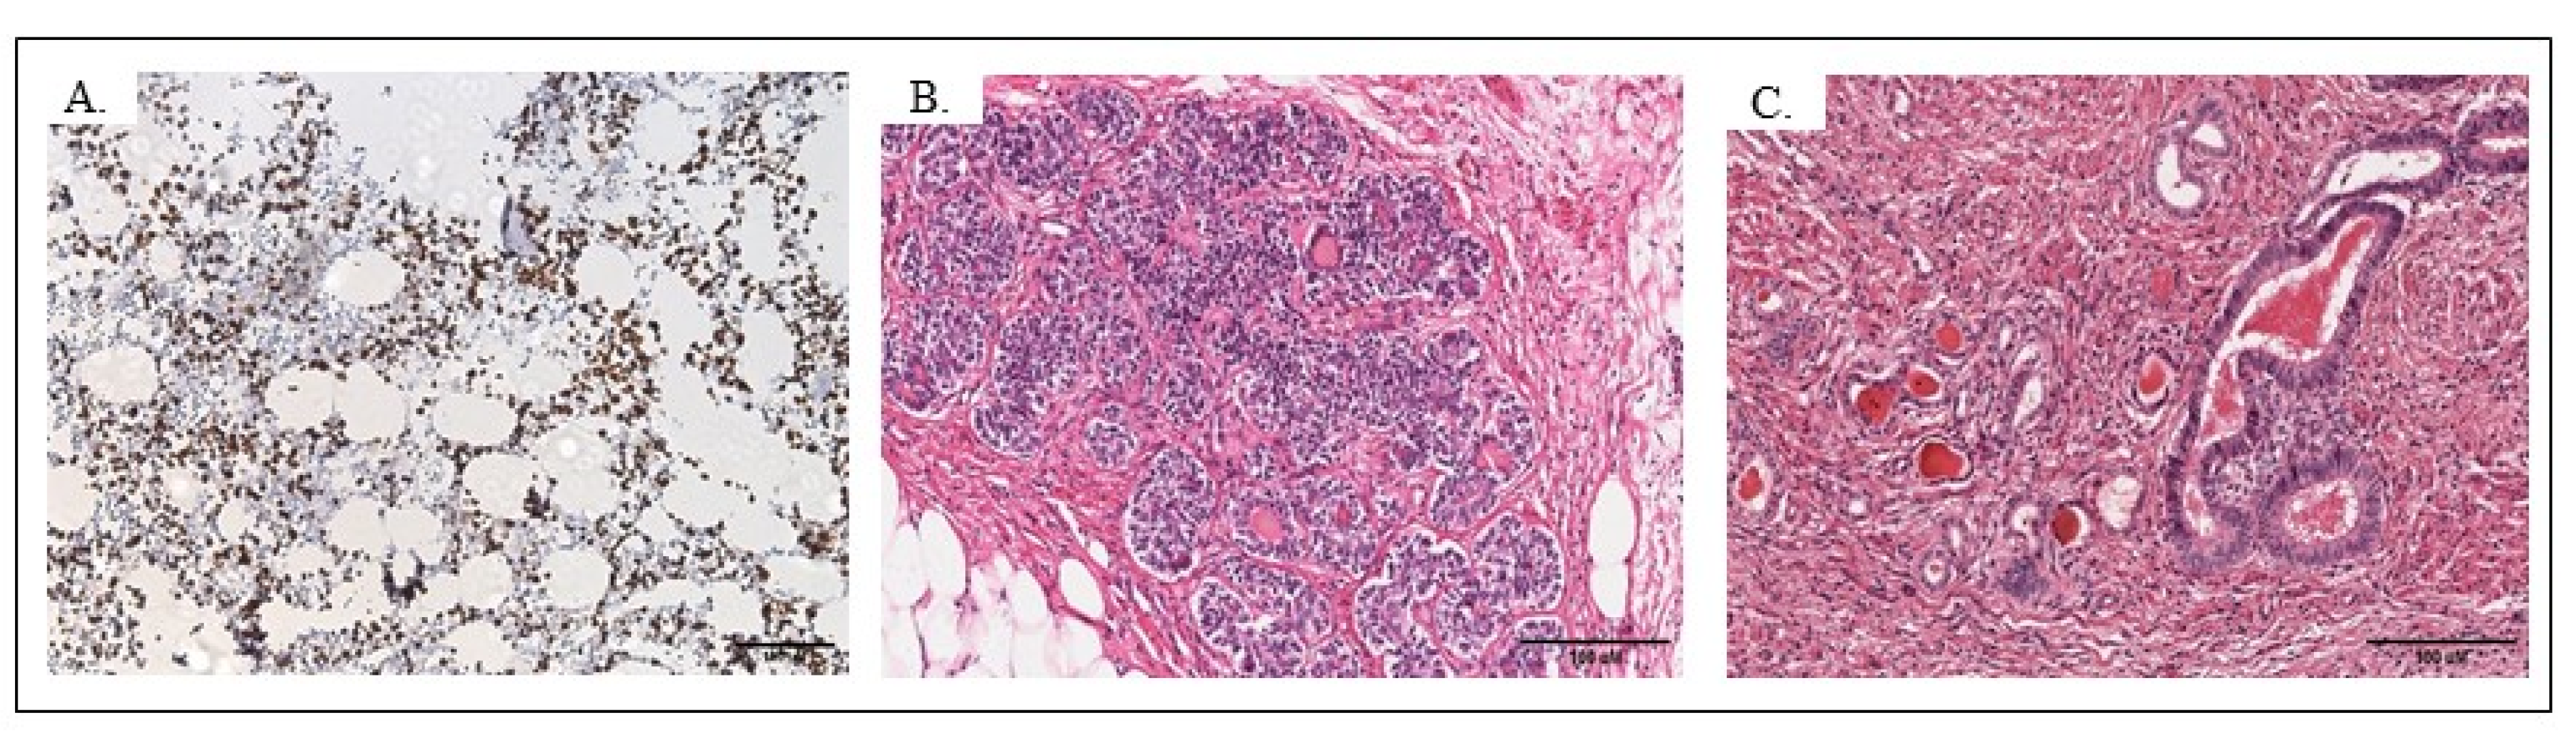

4.1. Histopathological Findings

4.1.1. TERATOMA

4.1.2. NET

4.2. Immunohistochemical Findings of NET

4.3. Immunohistochemical Findings of Teratoma